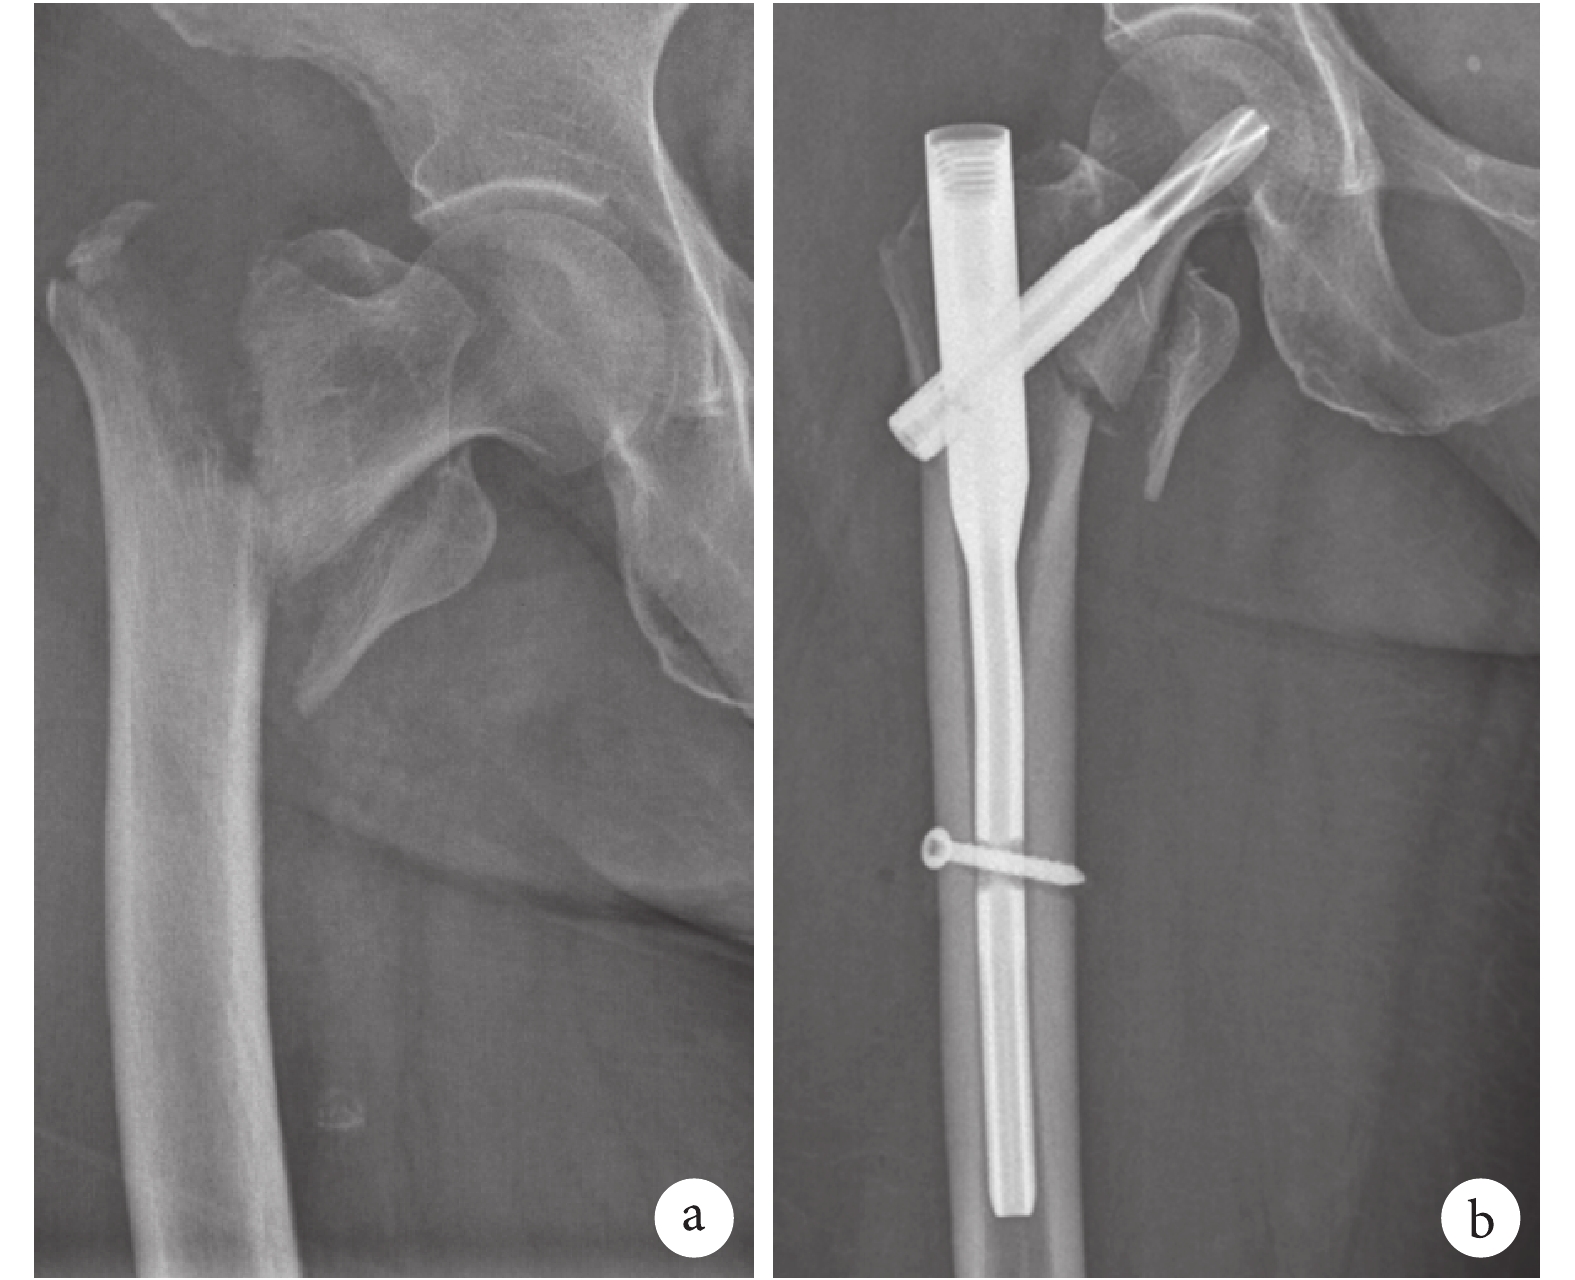

1.2.3 PFNA 組患者手術方法 患者取仰臥位,骨科牽引床牽引復位患肢,內旋約 5°,C 臂顯示骨折復位滿意后,根據患者肥胖程度,于股骨大轉子上方約 3~6 cm 行皮膚切口,捫及股骨大粗隆頂點后,插入導針至股骨髓腔內,大粗隆近段擴髓后插入主釘,確定插入深度后經定位器鉆入導針至股骨頭頸內,深度至股骨頭關節軟骨面下 5 mm,股骨外側骨皮質開口,將選用的螺旋刀片擊入,螺旋刀片位于股骨頭中心略微偏下,遠端采用 3.2~4.0 mm 長度鎖定螺釘固定,取除定位器后主釘擰入尾帽或填入骨蠟。見圖 1。